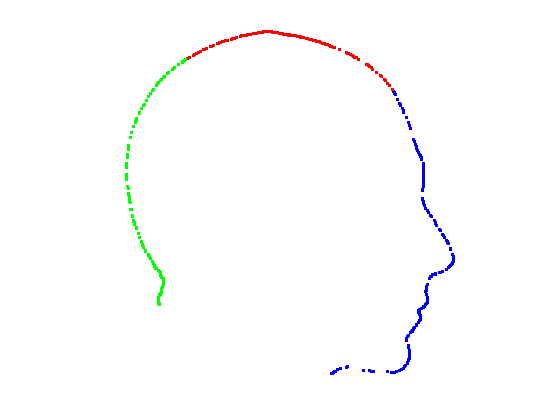

Given a set of points that lie on a symmetry plane, we divide the points into three groups by segmenting them at angles of 45 degrees and 135 degrees relative to the origin, as shown in Fig. 13. This gives us three profiles that we can model with spline functions.

|

|

|

|

For each of the three segments, we determine the range of gradients on that segment by simple differencing between consecutive points. Each segment is rotated into a 2D frame such that maximum absolute values of positive and negative gradients are equal. Cubic spline contours are fitted to the three profiles and the head profile contour is reconstructed using the three individual cubic splines. Fig. 14 show examples of these.

|

|

|

|